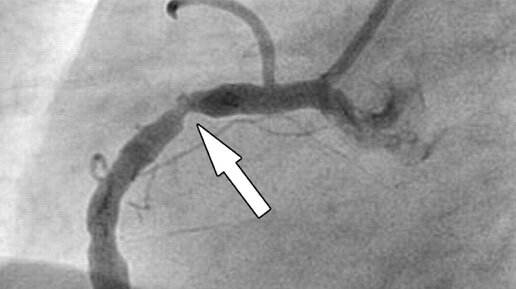

В 2023 году вышло очередное руководство American Heart Association в помощь врачам и пациентам, и посвященное лечению больных с хронической ишемической болезнью сердца. Если посмотреть на карту мира, где цветом отражена распространенность ИБС по регионам, то видно, что хотя у нас в России дела плохи, есть в мире регионы, где дела идут еще хуже: например, Северная Африка и Персидский залив. Самые основные положения этого многостраничного документа следующие: 1. Нефармакологические методы лечения, включая здоровое питание и физические упражнения, рекомендованы всем пациентам с хронической ИБС...